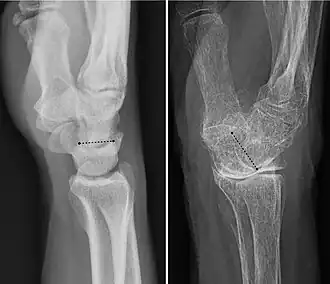

The radiocarpal (wrist) joint is an ellipsoid joint formed by the radius and the articular disc proximally and the proximal row of carpal bones distally. The carpal bones on the ulnar side only make intermittent contact with the proximal side — the triquetrum only makes contact during ulnar abduction. The capsule, lax and un-branched, is thin on the dorsal side and can contain synovial folds. The capsule is continuous with the midcarpal joint and strengthened by numerous ligaments, including the palmar and dorsal radiocarpal ligaments, and the ulnar and radial collateral ligaments. [6]

The parts forming the radiocarpal joint are the lower end of the radius and under surface of the articular disk above; and the scaphoid, lunate, and triquetral bones below. The articular surface of the radius and the undersurface of the articular disk form together with a transversely elliptical concave surface, the receiving cavity. The superior articular surfaces of the scaphoid, lunate, and triquetrum form a smooth convex surface, the condyle, which is received into the concavity.[7]

Articular surfaces

It has two articular surfaces named, proximal and distal articular surfaces respectively. The proximal articular surface is made up of the lower end of the radius and a triangular articular disc of the inferior radio-ulnar joint. On the other hand, the distal articular surface is made up of proximal surfaces of the scaphoid, triquetral and lunate bones.[11]